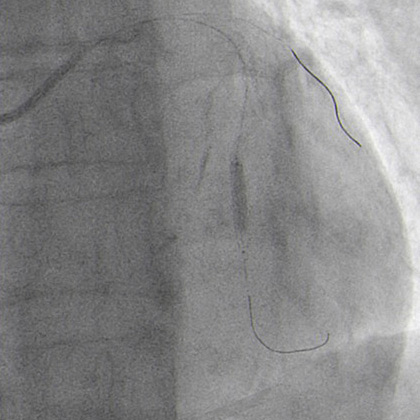

JR 4.0 guiding catheter exchanged with JL 4.0 to achieve left main (ping-pong) and position a parallel wire in left anterior descending (Figure 7.2). In the first wire we have the balloon, in the second wire a covered stent, but the perforation resolved only with balloon dilatation so we avoided, at this time to implant a covered stent.

JR 4.0 guiding catheter exchanged with JL 4.0 to achieve left main ping-pong (Figure 7.2).